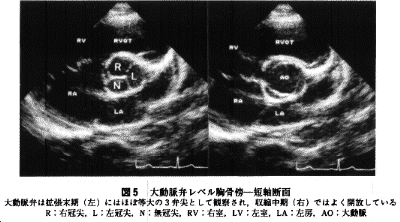

探触子を患者の頭側を見上げるように傾ける(探触子の頭は心尖方向に傾く、傾きが大きくなりすぎる場合は1肋間上方にずらす)と大動脈弁レベルでの短軸像が描出される(図5)。

a)大動脈弁はほぼ等しい大きさで三尖あるか

b)大動脈弁各弁尖の硬化や解放制限がないか